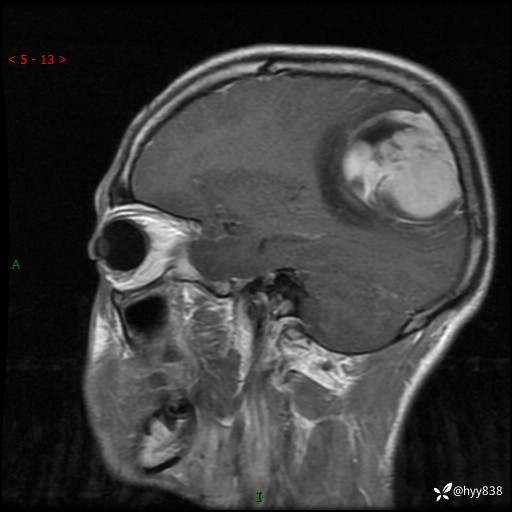

性别:男

年龄:21岁

简要病史:头痛伴呕吐半年,渐进性加重1月

颅脑MRI平扫+增强